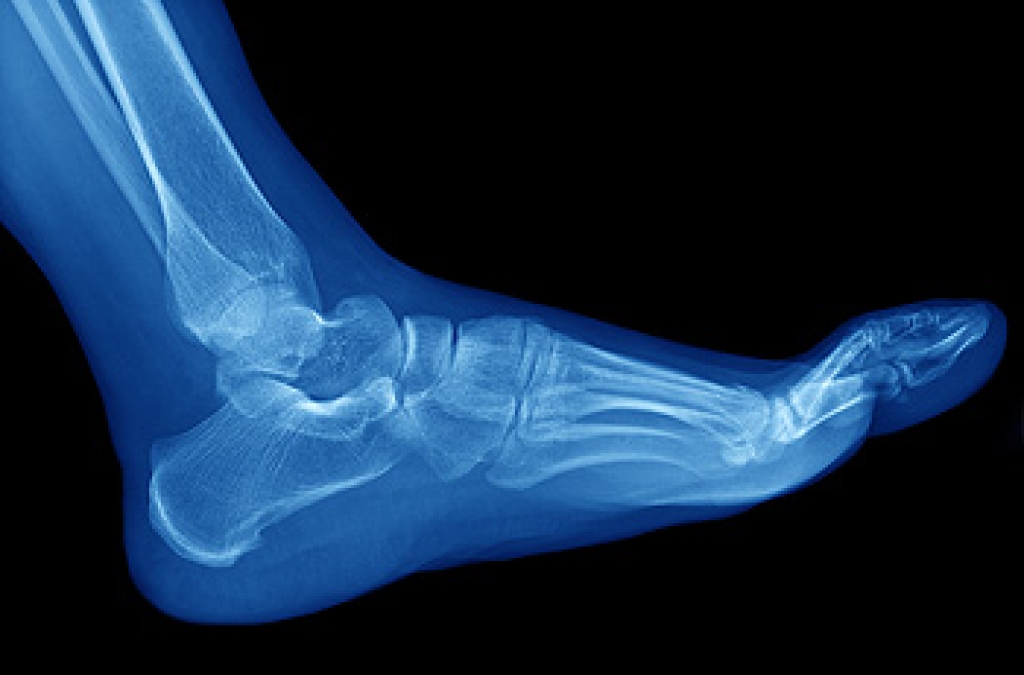

Standing on your feet for long periods of time can cause stress and pain in your feet. Your whole body may experience change in terms of posture, back pain, bunions, callouses and or plantar warts. There are ways to avoid these conditions with proper foot care, smart choices and correct posture.